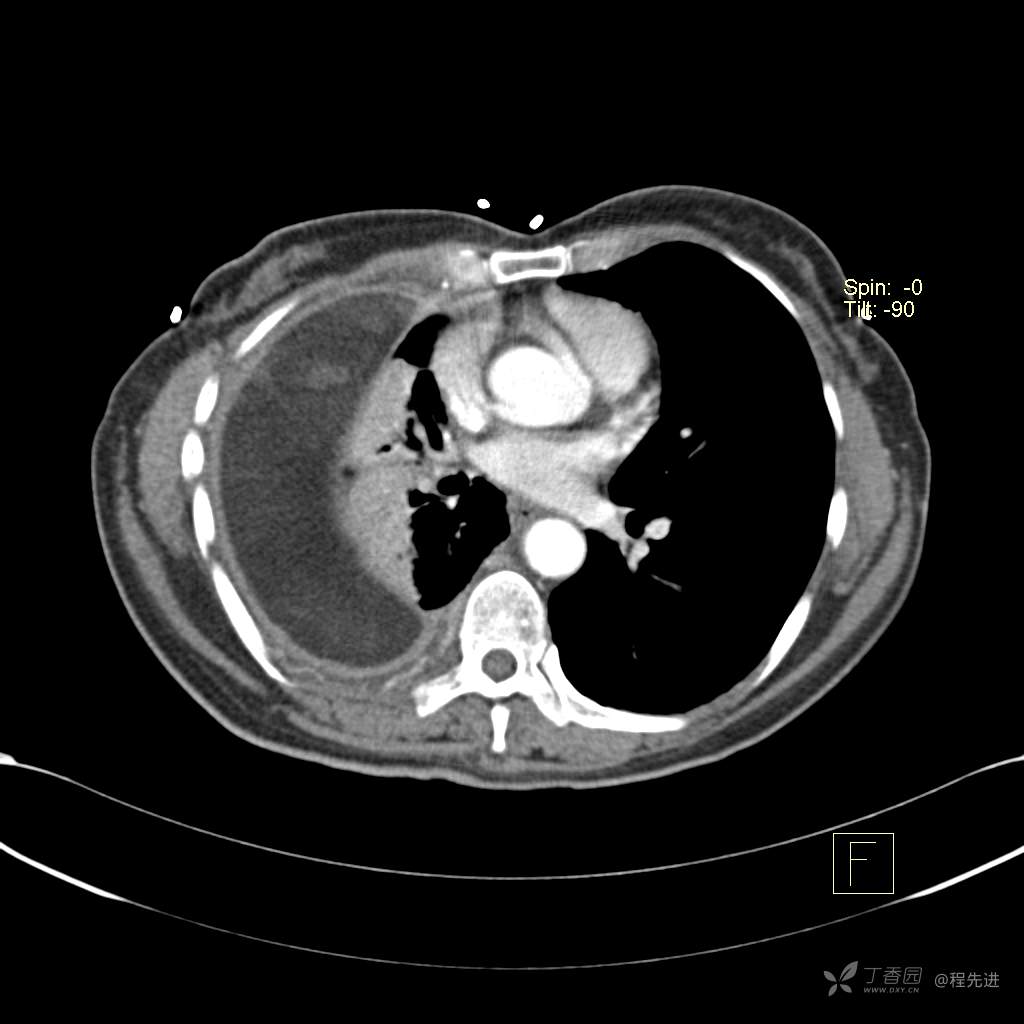

患者性别:女

患者年龄:51岁

简要病史:胸闷半年

肺淋巴管肌瘤病 (7)

乳糜胸 (8)